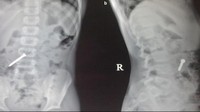

Seorang bocah empat tahun dilarikan ke rumah sakit karena mengalami nyeri perut selama 5-6 jam. Setelah dilakukan pemeriksaan, rontgen menunjukkan benda asing lingkaran berupa koin yang tidak sengaja tertelan. (Foto: F1000 Research)